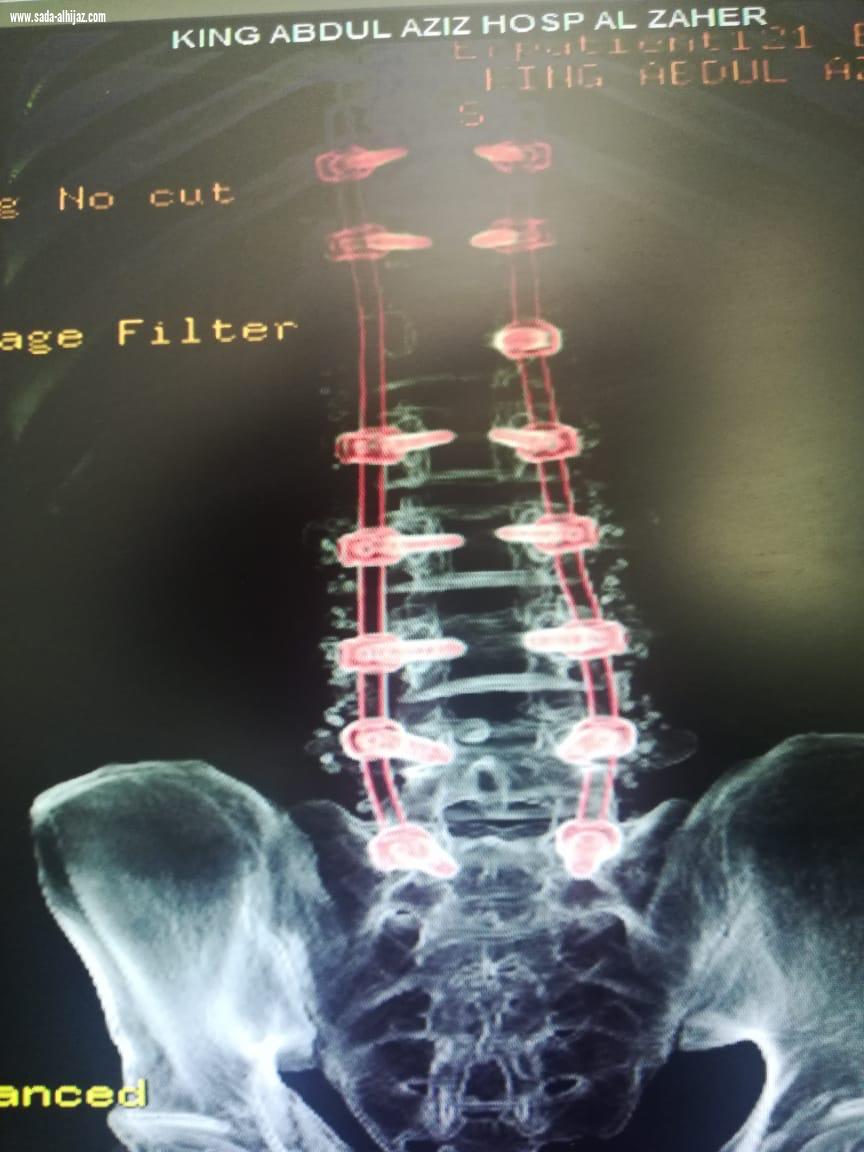

عبدالعزيزالنفيعي- الطائف تمكن فريق طبي بمستشفى الملك عبدالعزيز عضو التجمع الصحي بمكة بقسم جراحة المخ والأعصاب من إنقاذ حياة رجل يبلغ من العمر ( 30) تعرض لسقوط من الدور الخامس من إحدى البنايات بالعاصمة المقدسة . واوضح رئيس قسم جراحة المخ والاعصاب الدكتور زهير برناوي ان المصاب حضر إلى قسم الطوارئ بالمستشفى وهو يعاني من كسر مضاعف بالفقرة القطنية الاولى وكسر منضغط بالفقرة القطنية الرابعة وانزلاق غضروفي حاد بين الفقرتين الثانية والثالثة القطنية ونتج عن ذلك شلل نصفي وعدم التحكم بالإخراج وبعد عمل الاشعات والفحوصات اللازمة وعلى إثره دخل إلى غرفة العمليات، كحاله طارئة وتم اجراء عملية تثبيت للفقرات من الناحية الصدريه رقم ١١ وحتى العجزية رقم ١ مروراً بكل الفقرات القطنية الخمسة مع استئصال الغضروفي استغرقت العملية ( 8 ) ساعات وتم تنويم المصاب بالعناية المركزة لمدة يومين بقيادة استشاري جراحة المخ والاعصاب الدكتور محمد مرسي المشد وبفضل من الله تكللت العملية - بالنجاح، حيث تم نقل المصاب إلى قسم التنويم وخضع لعلاج دوائي وطبيعي الى ان استطاع السير على قدمية وهو بحالة مستقرة وتم خروجه من المستشفى.